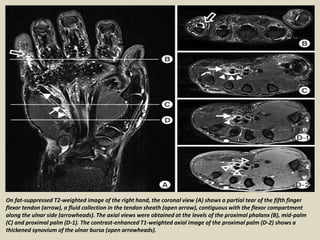

On fat-suppressed T2-weighted image of the right hand, the coronal view (A) shows a partial tear of the fifth finger

flexor tendon (arrow), a fluid collection in the tendon sheath (open arrow), contiguous with the flexor compartment

along the ulnar side (arrowheads). The axial views were obtained at the levels of the proximal phalanx (B), mid-palm

(C) and proximal palm (D-1). The contrast-enhanced T1-weighted axial image of the proximal palm (D-2) shows a

thickened synovium of the ulnar bursa (open arrowheads).